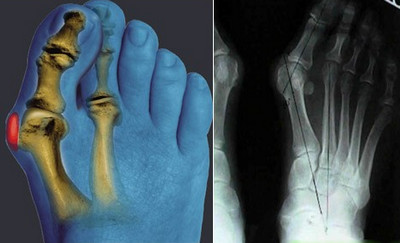

При деформирующем остеоартрозе применяются следующие методы оперативного лечения:

- Артродез (чаще всего выполняется при поражении мелких суставов пальцев рук или ног, а также при проблемах с голеностопом);

- Остеотомия (данная операция предполагает механическую коррекцию деформированной формы сустава, обычно проводится при поражении крупных суставов);

- Эндопротезирование (в основном, это замена суставных элементов в наиболее подвижных сочленениях, таких как колено или тазобедренный сустав).